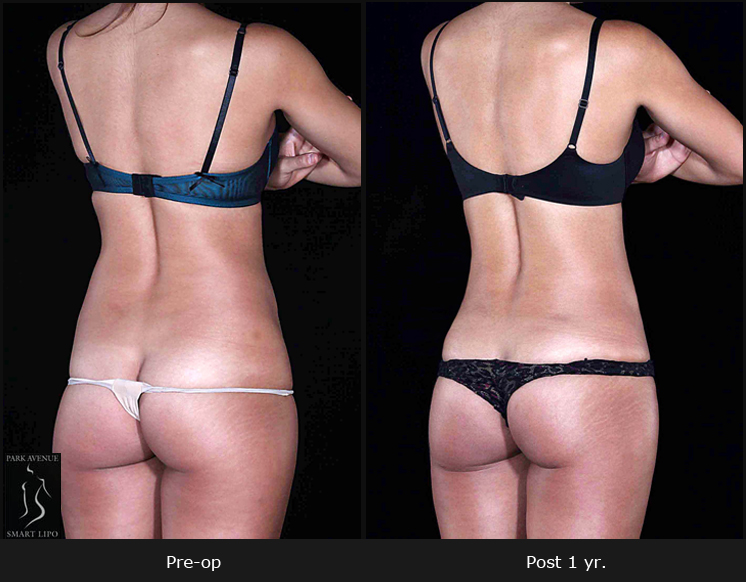

Gynecomastia surgery or male breast reduction addresses oversized male breasts. The procedure involves removes excess fat and glandular tissue, reducing the size and shape of the breasts to create a more masculine physique. This procedure can provide a long-lasting...

Gynecomastia or excessive build-up of male breast tissue can be effectively addressed with SmartLipo laser liposuction in a professional NYC plastic surgery facility. The procedure involves removing the excess fat by liquefying it using laser energy. Characterized by...